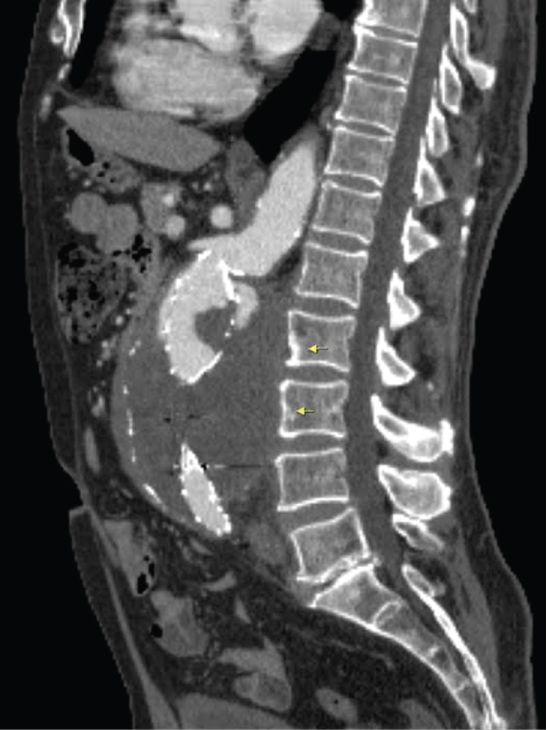

Case 2: A 80-year-old man was under follow up assessments due to deteriorated general health status after the failed operation for AAA. The chronic contained ruptured aortic aneurysm (CCAA) and erosion at the anterior corpus of the adjacent vertebra were established with CT (Figure 3 and Figure 4).

Figure 3: A 80-year-old man, operated abdominal aortic aneurysm. Sagittal reformate CT image: Aortic aneurysm with diameter of 85 mm and erosion at the anterior corpus of the adjacent vertebra (L2) is seen (long arrow). View Figure 3